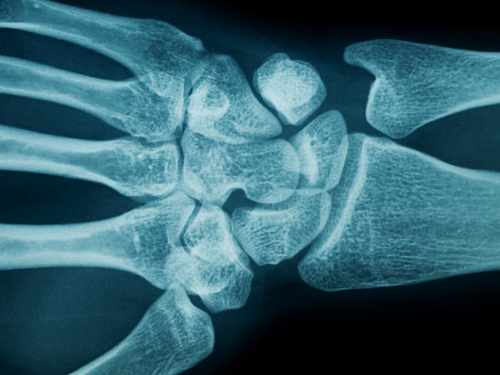

Ασθενείς που έχουν υποστεί ένα οστεοπορωτικό κάταγμα έχουν αυξημένο κίνδυνο εμφάνισης ενός επόμενου κατάγματος κατά 86%. Το συντριπτικό ποσοστό των οστεοπορωτικών καταγμάτων αφορούν την σπονδυλική στήλη, την πηχεοκαρπική άρθρωση και το ισχίο. Επίσης, οστεοπορωτικά κατάγματα μπορούν να εμφανιστούν σε άλλα οστά. Υπάρχει περίπτωση το κάταγμα να εκδηλώνεται με την εμφάνιση έντονου και αιφνίδιου πόνου στην πλάτη ή την οσφυϊκή μοίρα της ΣΣ και χωρίς να έχει προηγηθεί τραυματισμός.

Διάγνωση Οστεοπόρωσης

Η διάγνωση της οστεοπόρωσης είναι απλή και γίνεται με την μέτρηση της οστικής πυκνότητας. Η οστική πυκνότητα (bone mineral density-BMD, g/cm2), αποτελεί την καθιερωμένη μέθοδο διάγνωσης της οστεοπόρωσης και παρακολούθησης των οστεοπορωτικών ασθενών.